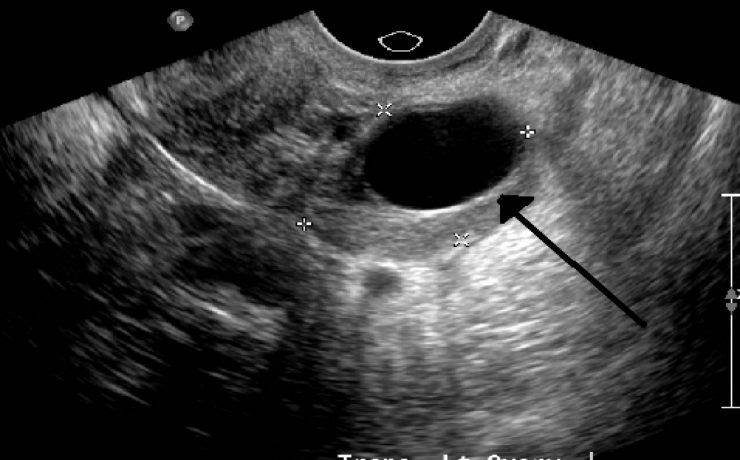

Defectos congénitos asociados con translucencia nucal aumentada La translucencia nucal es una anomalía que se forma en el feto y puede ser detectada por ultrasonido durante el primer trimestre del embarazo, entre la semana 10 y 14. Por lo general, desaparece entre la semana 18 y 20 de gestación. Este